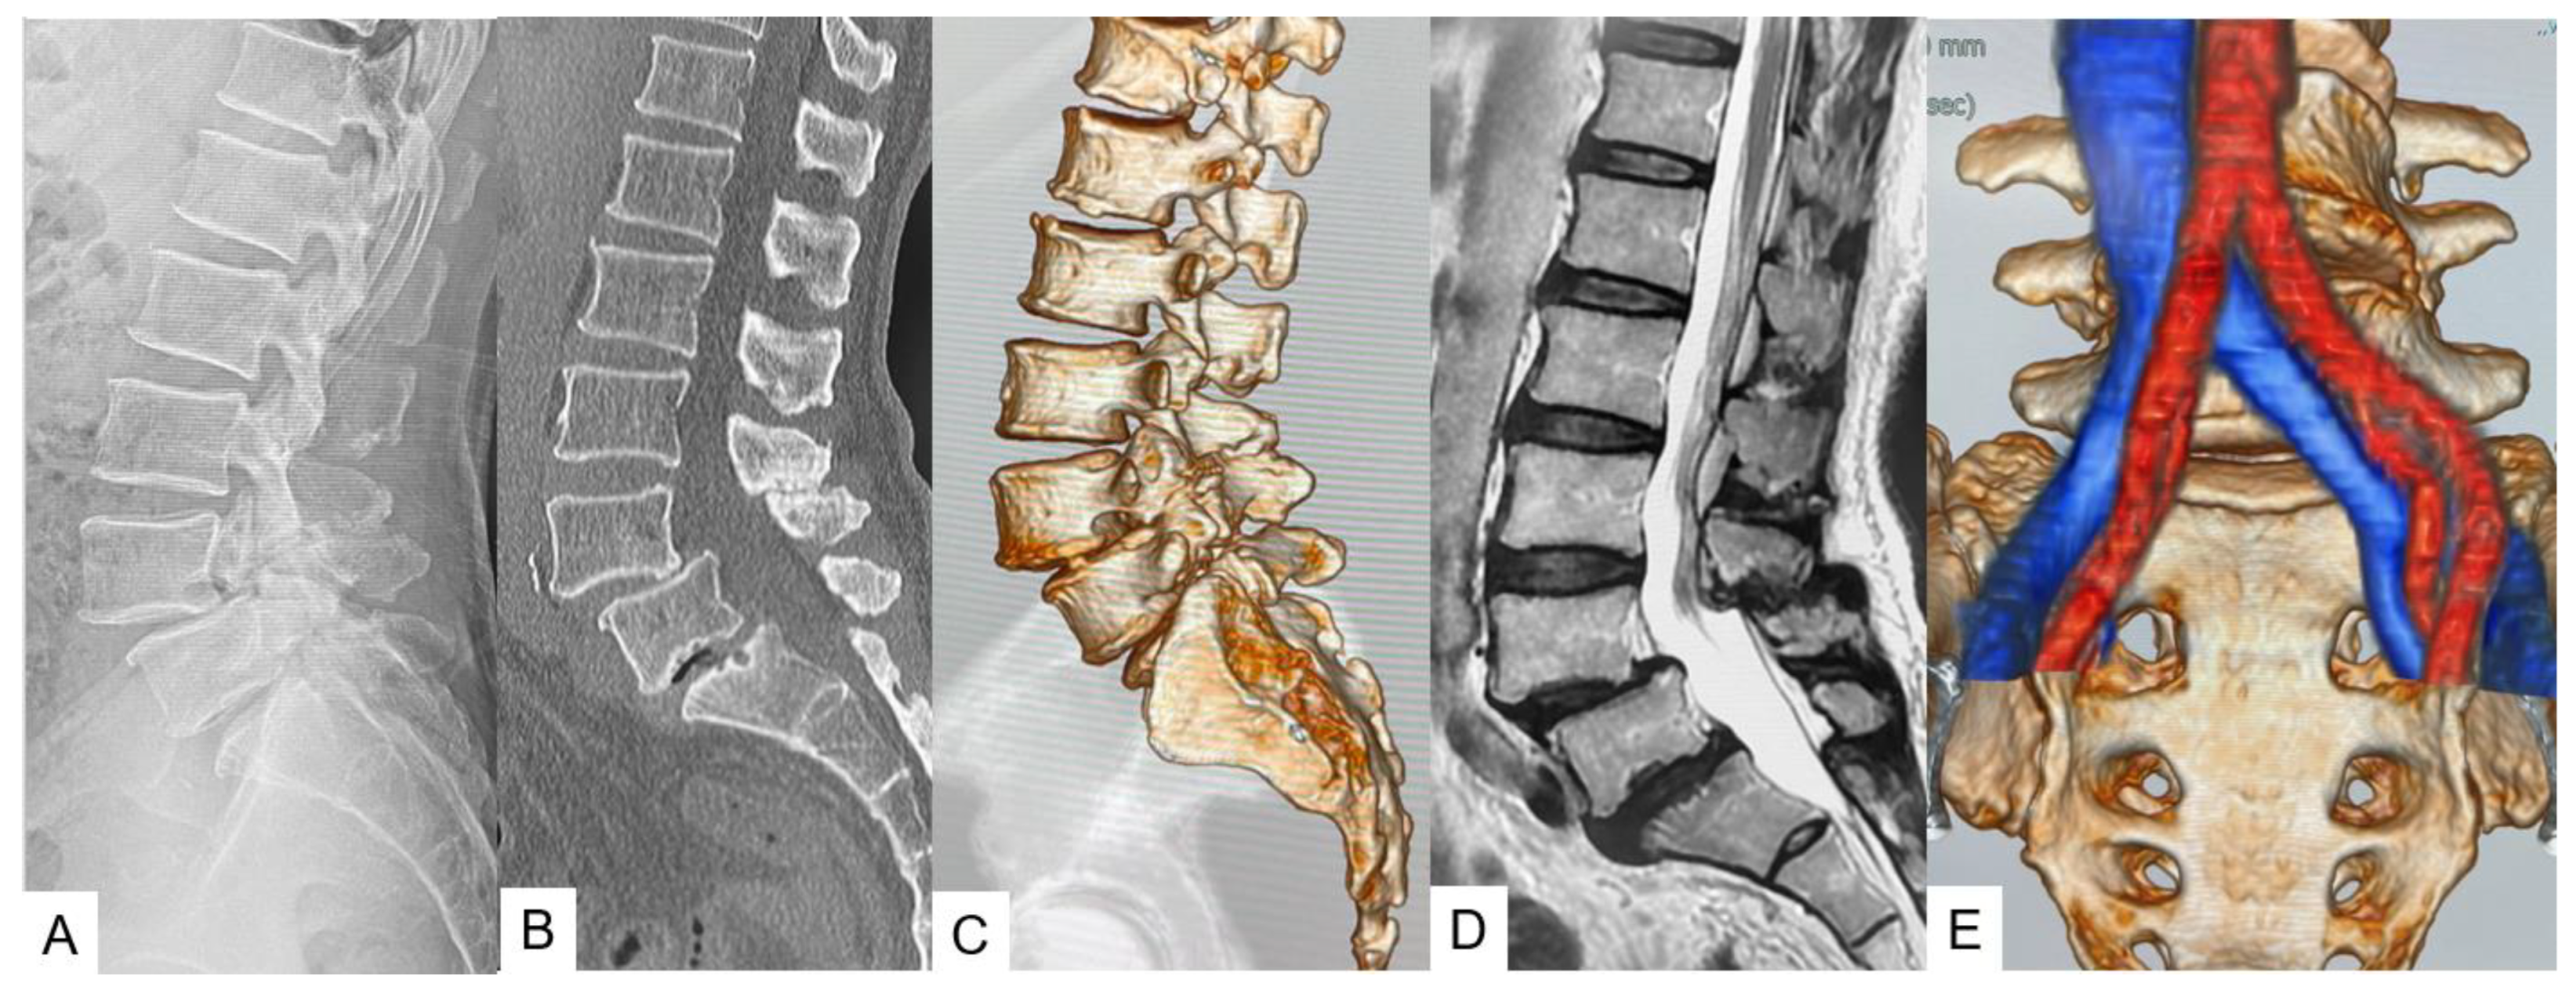

- Tanaka, M.; Sonawane, S.; Meena, U.; Lu, Z.; Fujiwara, Y.; Taoka, T.; Uotani, K.; Oda, Y.; Sakaguchi, T.; Arataki, S. Comparison of C-Arm-Free Oblique Lumbar Interbody Fusion L5-S1 (OLIF51) with Transforaminal Lumbar Interbody Fusion L5-S1 (TLIF51) for Adult Spinal Deformity. Medicina 2023, 59, 838. [Google Scholar] [CrossRef] [PubMed]

- Zygogiannis, K.; Tanaka, M.; Sake, N.; Arataki, S.; Fujiwara, Y.; Taoka, T.; Uotani, K.; Askar, A.E.K.A.; Chatzikomninos, I. Our C-Arm-Free Minimally Invasive Technique for Spinal Surgery: The Thoracolumbar and Lumbar Spine-Based on Our Experiences. Medicina 2023, 59, 2116. [Google Scholar] [CrossRef] [PubMed]

- Tan, Y.; Tanaka, M.; Sonawane, S.; Uotani, K.; Oda, Y.; Fujiwara, Y.; Arataki, S.; Yamauchi, T.; Takigawa, T.; Ito, Y. Comparison of Simultaneous Single-Position Oblique Lumbar Interbody Fusion and Percutaneous Pedicle Screw Fixation with Posterior Lumbar Interbody Fusion Using O-Arm Navigated Technique for Lumbar Degenerative Diseases. J. Clin. Med. 2021, 10, 4938. [Google Scholar] [CrossRef] [PubMed]

- Tanaka, M.; Sonawane, S.; Uotani, K.; Fujiwara, Y.; Sessumpun, K.; Yamauchi, T.; Sugihara, S. Percutaneous C-Arm Free O-Arm Navigated Biopsy for Spinal Pathologies: A Technical Note. Diagnostics 2021, 11, 636. [Google Scholar] [CrossRef]